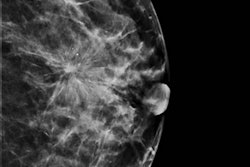

France's union of private radiologists (Fédération Nationale des Médecins Radiologues, FNMR) has announced the start of its new initiative for "Pink October" to encourage women to get screened for breast cancer. The campaign comprises a full-page advert to promote screening in the magazine Elle (4 and 18 October editions), in addition to FNMR brochures to be handed out at 100 L'Oréal hairdressing salons across France throughout the month.

The Pink October advert. Image courtesy of the FNMR.Speaking to AuntMinnieEurope.com ahead of the official launch on 3 October, FNMR President Dr. Jean-Philippe Masson described how the organization has tried different strategies each year for Pink October, and the latest drive comes in the wake of TV and radio commercials in 2017 and 2018, respectively.